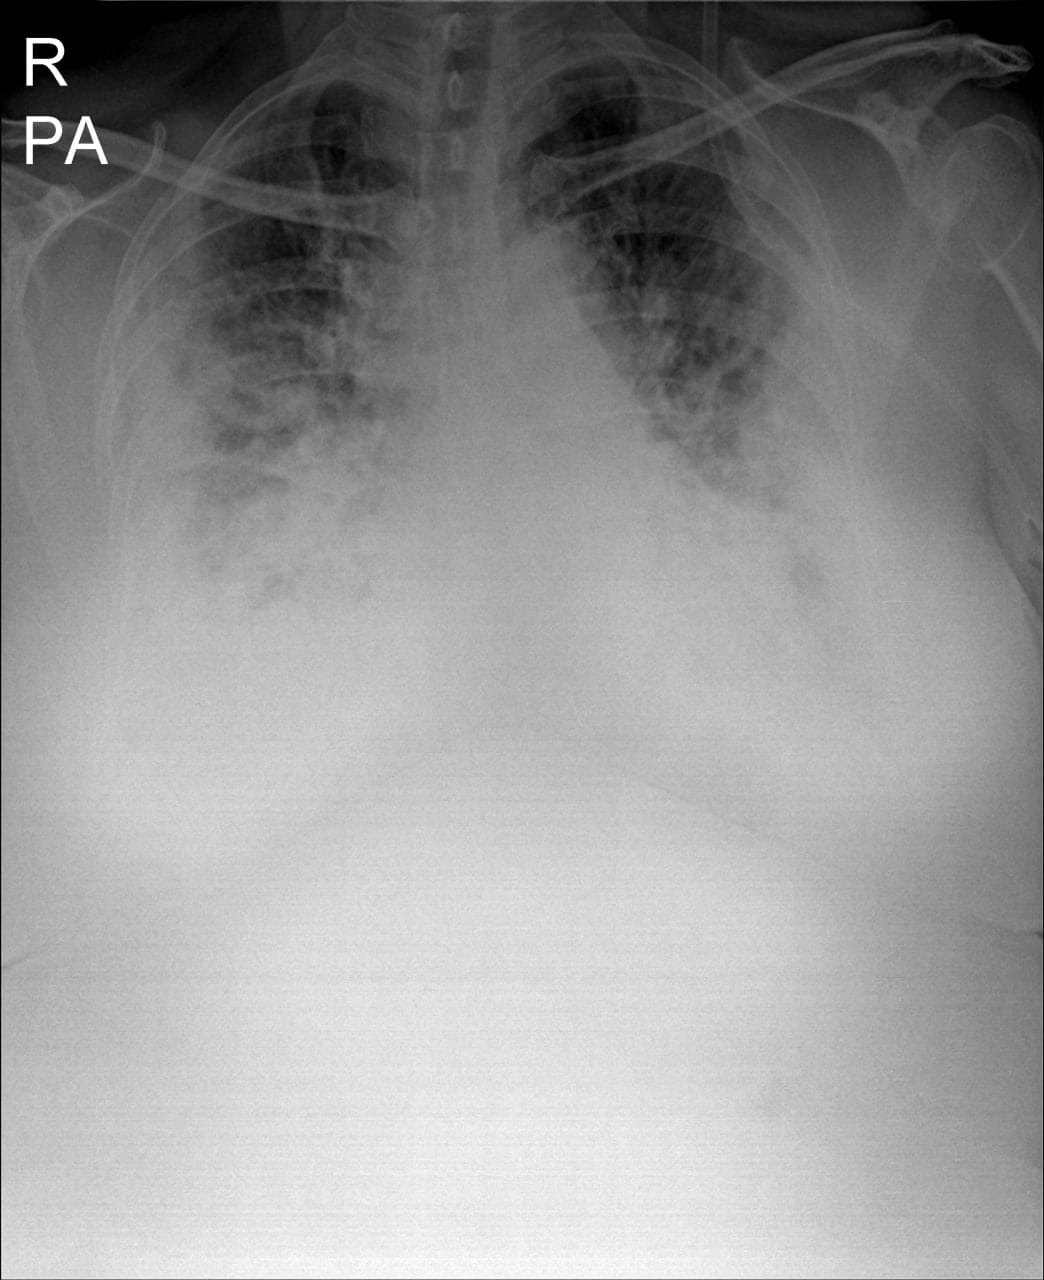

“មានបទពិសោធន៍ជាង1ឆ្នាំក្នុងគ្រប់គ្រង និងព្យាបាលជំងឺកូវីដដោយគ្មានការភ័យខ្លាចឬតក់ស្លុតឡើយ ។ តែក្នុង1ខែចុងក្រោយនេះចាប់ពី 20 កុម្ភៈ 2021 ខ្ញុំមានអារម្មណ៍ភ័យខ្លាច និងព្រួយបារម្ភណាស់ ពីព្រោះវាជាប្រភេទមេរោគប្រែរូបថ្មី (variant virus strain) ដែលក្នុងរយៈពេលតែ2ទៅ5ថ្ងៃវាវាយលុកចូលសួតធ្វើអោយរលាកធ្ងន់ធ្ងរទាំងសងខាង ។ រូបភាពសួតត្រូវបានមេរោគស៊ីសុះសាច់ដ៏គួអោយខ្លាច ។